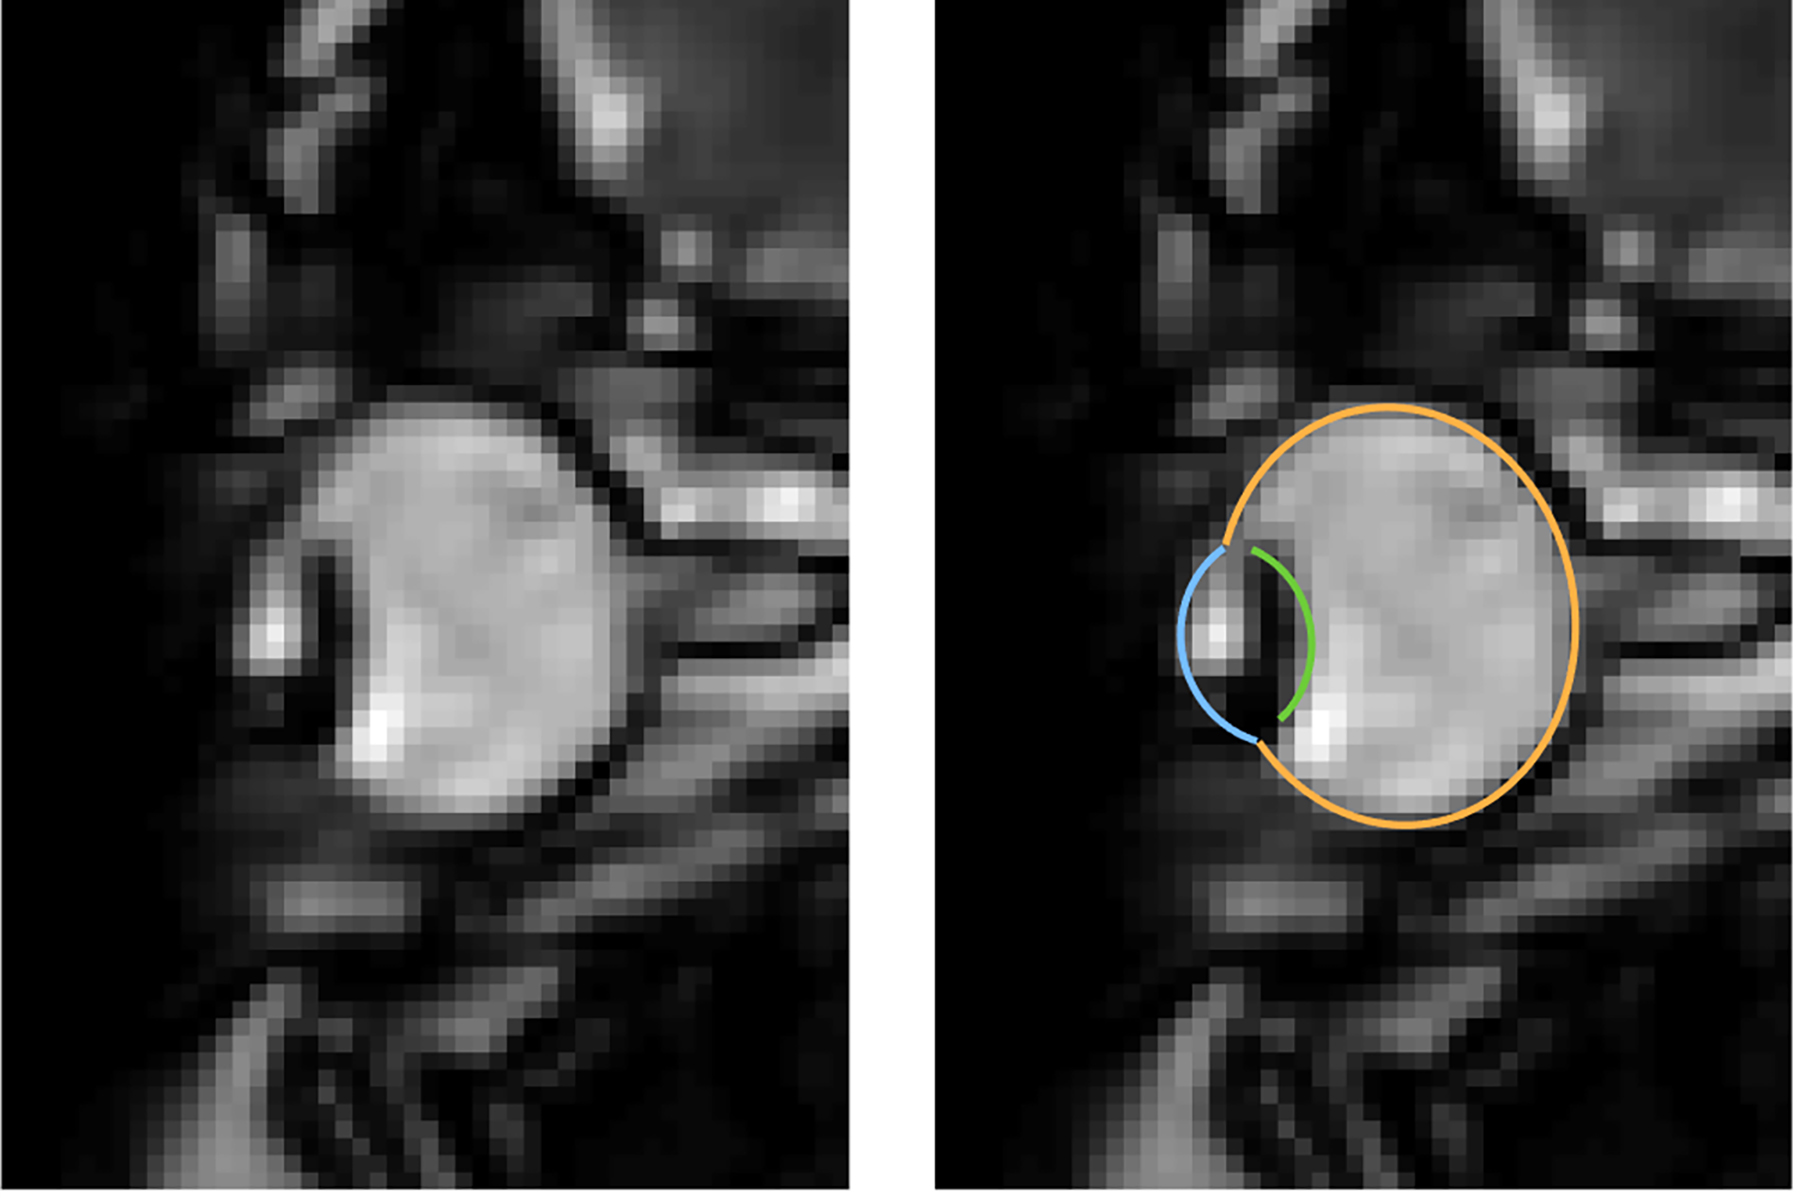

Scientists from Westfälische Wilhelms-Universität (WWU) Münster have developed a method to measure the full extent of eye movements during blinks for the first time. The new method uses Magnetic Resonance Imaging (MRI), to take many fast measurements of an entire cross-section of the eye, unlike most common eye tracking that measures only the front of the eyeball. This allows measurements even when the eye is closed, additional assessment of the ocular muscles and visualises displacements and deformations of the whole eyeball. The study describing the new method has been published in the scientific journal “eNeuro”.

MRI is a relatively slow procedure, the temporal resolution usually ranges between seconds or minutes. Eye movements on the other hand are fast and typically last only a few dozen milliseconds. Recent technological advances allowed the recording of 2-D MR images at a resolution of up to 20 milliseconds. Those ultrafast MR sequences were initially developed for cardiac imaging and haven’t been applied to the recording of eye movements. “We could reach a temporal resolution of 35 milliseconds. Total scan duration of only a few minutes already leads to the acquisition of over 10000 images. For actual eye-tracking, a fully automatic segmentation algorithm to analyse these images was needed”, explains co-author Prof. Markus Lappe, professor for cognitive neuroscience at the Institute of Psychology at the University of Münster. “With ‘MREyeTrack’ we have developed such a segmentation algorithm, which allows the fully-automated analysis of eye position and orientation in every single image.”